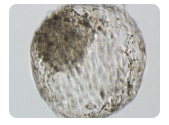

在辅助生殖技术领域,试管婴儿(IVF)和人工授精(AI)是两种常用的方法,它们各自具有独特的治疗原理和适用范围。本文将从多个方面探讨试管婴儿和人工授精的区别,并

在生殖医学领域,人工授精和试管婴儿是两种常见的辅助生殖技术,它们为许多不孕不育的夫妇带来了生育的希望。然而,许多人对这两种技术存在误解,尤其是将人工授精与试管婴